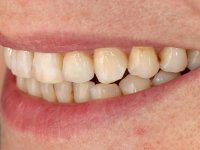

The patient complained that she had a front tooth shaking, did not like the "dark canine" and also "wanted to close the spaces between the teeth”. After 8 years of initial treatment, what motivated a second treatment phase was that the "two front teeth are ugly."

Female patient, 47 years old non-smoker. Tooth 1.3 with endodontic treatment and a cast post and core, rehabilitated with a provisional crown. The two upper lateral incisors are conoid and of small dimension. Tooth 2.2 presents mobility, in agreement with a significant bone reabsorption between teeth 2.1 and 2.3. The two central incisors are separated by a 3 mm diastema and tooth 2.3 presents a crossed occlusion with the opposing tooth. There is also an absence of some posterior teeth and reasonable oral hygiene. In the second intervention performed 8 years later, it was verified that the upper central incisors were chromatically darker and had a longitudinal groove in the enamel which, being pigmented, aesthetically compromised the smile. The work performed in the first phase of the treatment was competent, aesthetically and functionally. Finally, one year after the last intervention, the patient complained of a fracture on the veneer placed on tooth 2.1, probably as a result of being in contact with the abutment of the implant. The rigidity of implant ankylosis may have been the cause of this fracture. I have observed other instances of this type of fracture in identical clinical situations. The veneer of tooth 1.2 was aesthetically compromised and the dental structure itself had small caries and, therefore, its replacement would be recommended.

This addition of resin would guide the ceramist in the final placement of the gingival tonality ceramic. The crown that would rehabilitate tooth 1.3 was cemented in this test session with glass ionomer cement, reinforced with composite resin. Once the laboratory work was finished on the veneer for tooth 1.2, the abutment, and the veneer for the implant, this was bonded in the mouth, after placement of the absolute insulation. The work completely satisfied the patient. For eight years, the patient had periodical check-ups, and was pleased with the treatment, but also began to show interest in an aesthetical intervention on the upper central incisors. Once the second phase of our intervention was decided, dental preparation of teeth 1.1 and 2.1 was performed for the placement of two feldspathic veneers. Particular care was taken in the distal inter-proximal preparation adjacent to the abutment of the implant.

The axis of insertion of the veneer in relation to the abutment was very carefully evaluated. The feldspathic veneers were prepared in the laboratory and then bonded to the mouth after placing absolute insulation. One year later, we began our third phase of treatment, after the veneer in tooth 2.1 fractured. A dental preparation was done on the bonded veneer, seeking to extend the distal inter-proximal interface more to the palate. The objective would be to move the veneer to a more palatine contact point. Preparation of tooth 1.2 was limited to creating an insertion axis. After preparation, the total crown and laboratory veneer were bonded to the mouth. First, the crown was bonded using a relative insulation with Teflon, later the veneer was bonded after the absolute insulation placement. In the crown, I used this type of insulation to avoid the use of staples. It would be difficult to apply due to the shape and size of the tooth, and would also be aggressive to the soft tissues. After bonding procedures, the occlusal integration of the work was evaluated.